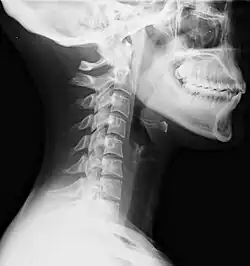

| Lateral view X-ray of whiplash showing a loss of normal lordosis of the cervical vertebrae | |

Diagnosis occurs through a patient history, head and neck examination, X-rays to rule out bone fractures and may involve the use of medical imaging to determine if there are other injuries.[28]